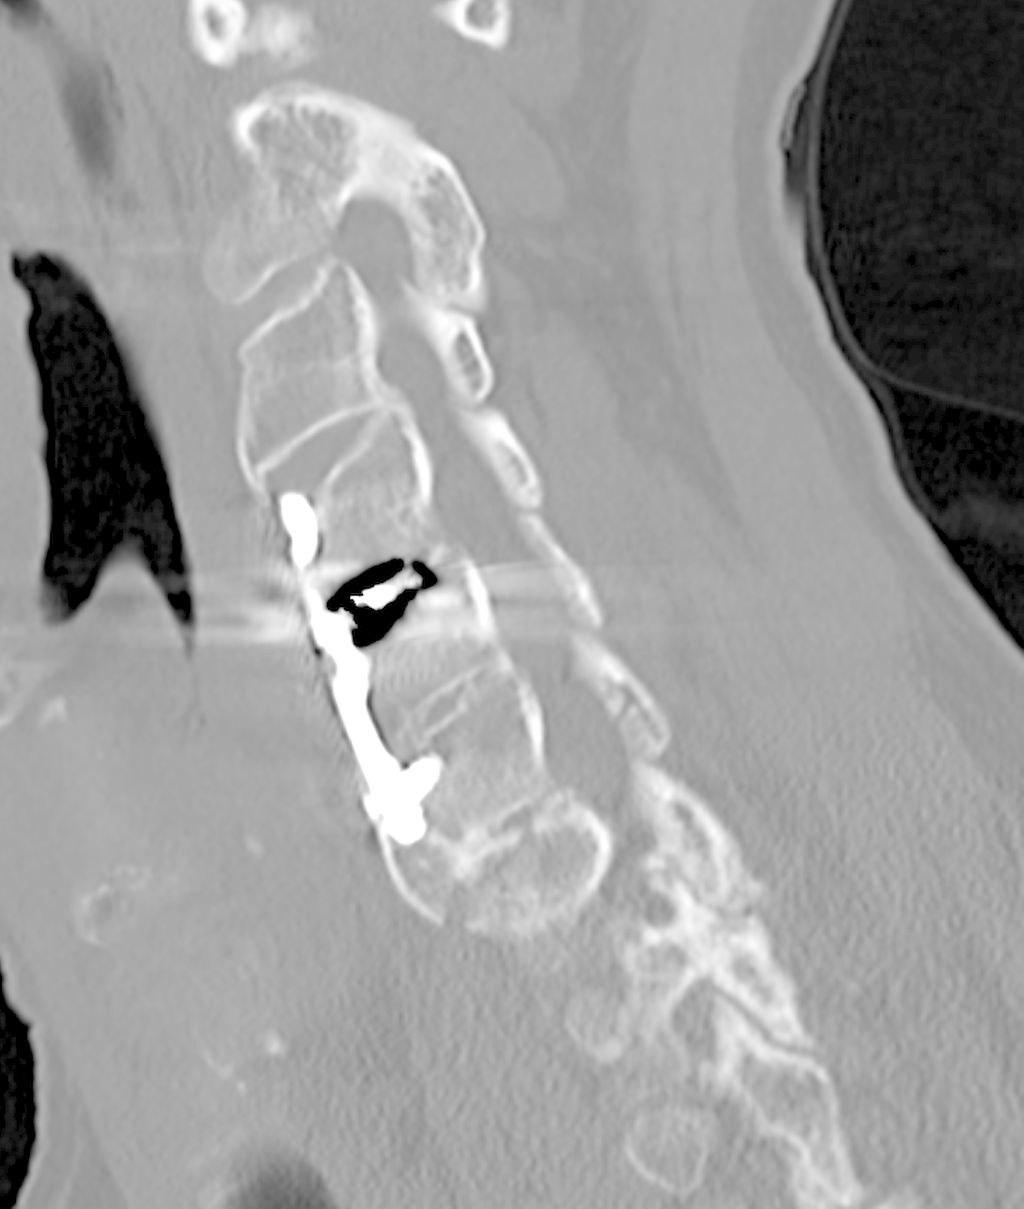

Beispiel für die Implantation zervikaler Pedikelschrauben. In diesem Fall kam es bei einem 61-jährigen Patienten 10 Jahre nach anteriorer zervikaler Diskektomie und Fusion (ACDF) C4/5 und ventraler Verplattung C4–6 zu einer Ankylosierung auch von C6/7. Nach Sturz kam es zu einer Fraktur bei C6/7 mit begleitender Bogenfraktur und auch Beteiligung der dorsalen Ligamenta (Abb. 1 und 2). Klinisch bestanden ausgeprägte Nackenschmerzen und kein neurologisches Defizit. Es wurde die Indikation der dorsalen Verschraubung von C4 auf Th1 gestellt. Intraoperativ wurde routinemäßig zusätzlich eine kleine Referenzschraube in einer Lamina – entfernt von der Dornfortsatz-Referenzklemme für die Navigation – gesetzt. Mit dieser konnte intraoperativ die Genauigkeit der Navigation exakt überprüft werden (Abb. 4 und 5). Mittels navigierter High-Speed-Fräse wurden die Schraubenkanäle vorgebohrt (Abb. 6), im Anschluss wurde der Bohrkanal ausgetastet und die Schrauben wurden implantiert. Abbildung 7 zeigt eine Röntgenkontrolle 3 Monate postoperativ.

Abb. 4: Screenshot der Navigationssoftware intraoperativ (Stealth Station S7). Es erfolgt die intraoperative Verifizierung der Navigationsgenauigkeit mittels kleiner Schraube in der Lamina, positioniert idealerweise entfernt von der Dornfortsatz-Referenzklemme. Die navigierte Fräse wird im Situs exakt auf die Schraubenmitte gerichtet, und die Navigation bestätigt die Genauigkeit | |